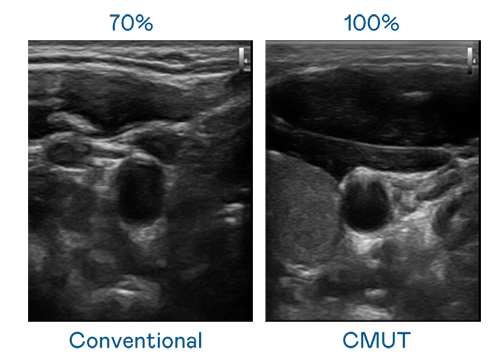

CMUT 技术是一种用电容式微机电元件来产生超音波讯号的技术。与传统 PZT 压电式技术相比,CMUT 频宽增加 30%,更宽频的超音波讯号让影像解析度大幅提升,是实现高影像品质医疗超音波扫描、促进精准医疗发展的关键技术。

大频宽带来超清晰影像

超音波影像的解析度高低,首先取决于探头能发出的讯号频宽。G22恒峰 CMUT 可提供高清晰的超音波讯号,提供高频宽、高灵敏度、影像纹理细节更高的超音波影像,协助医护人员缩短影像判读时间及利用精准的医疗影像进行诊断。